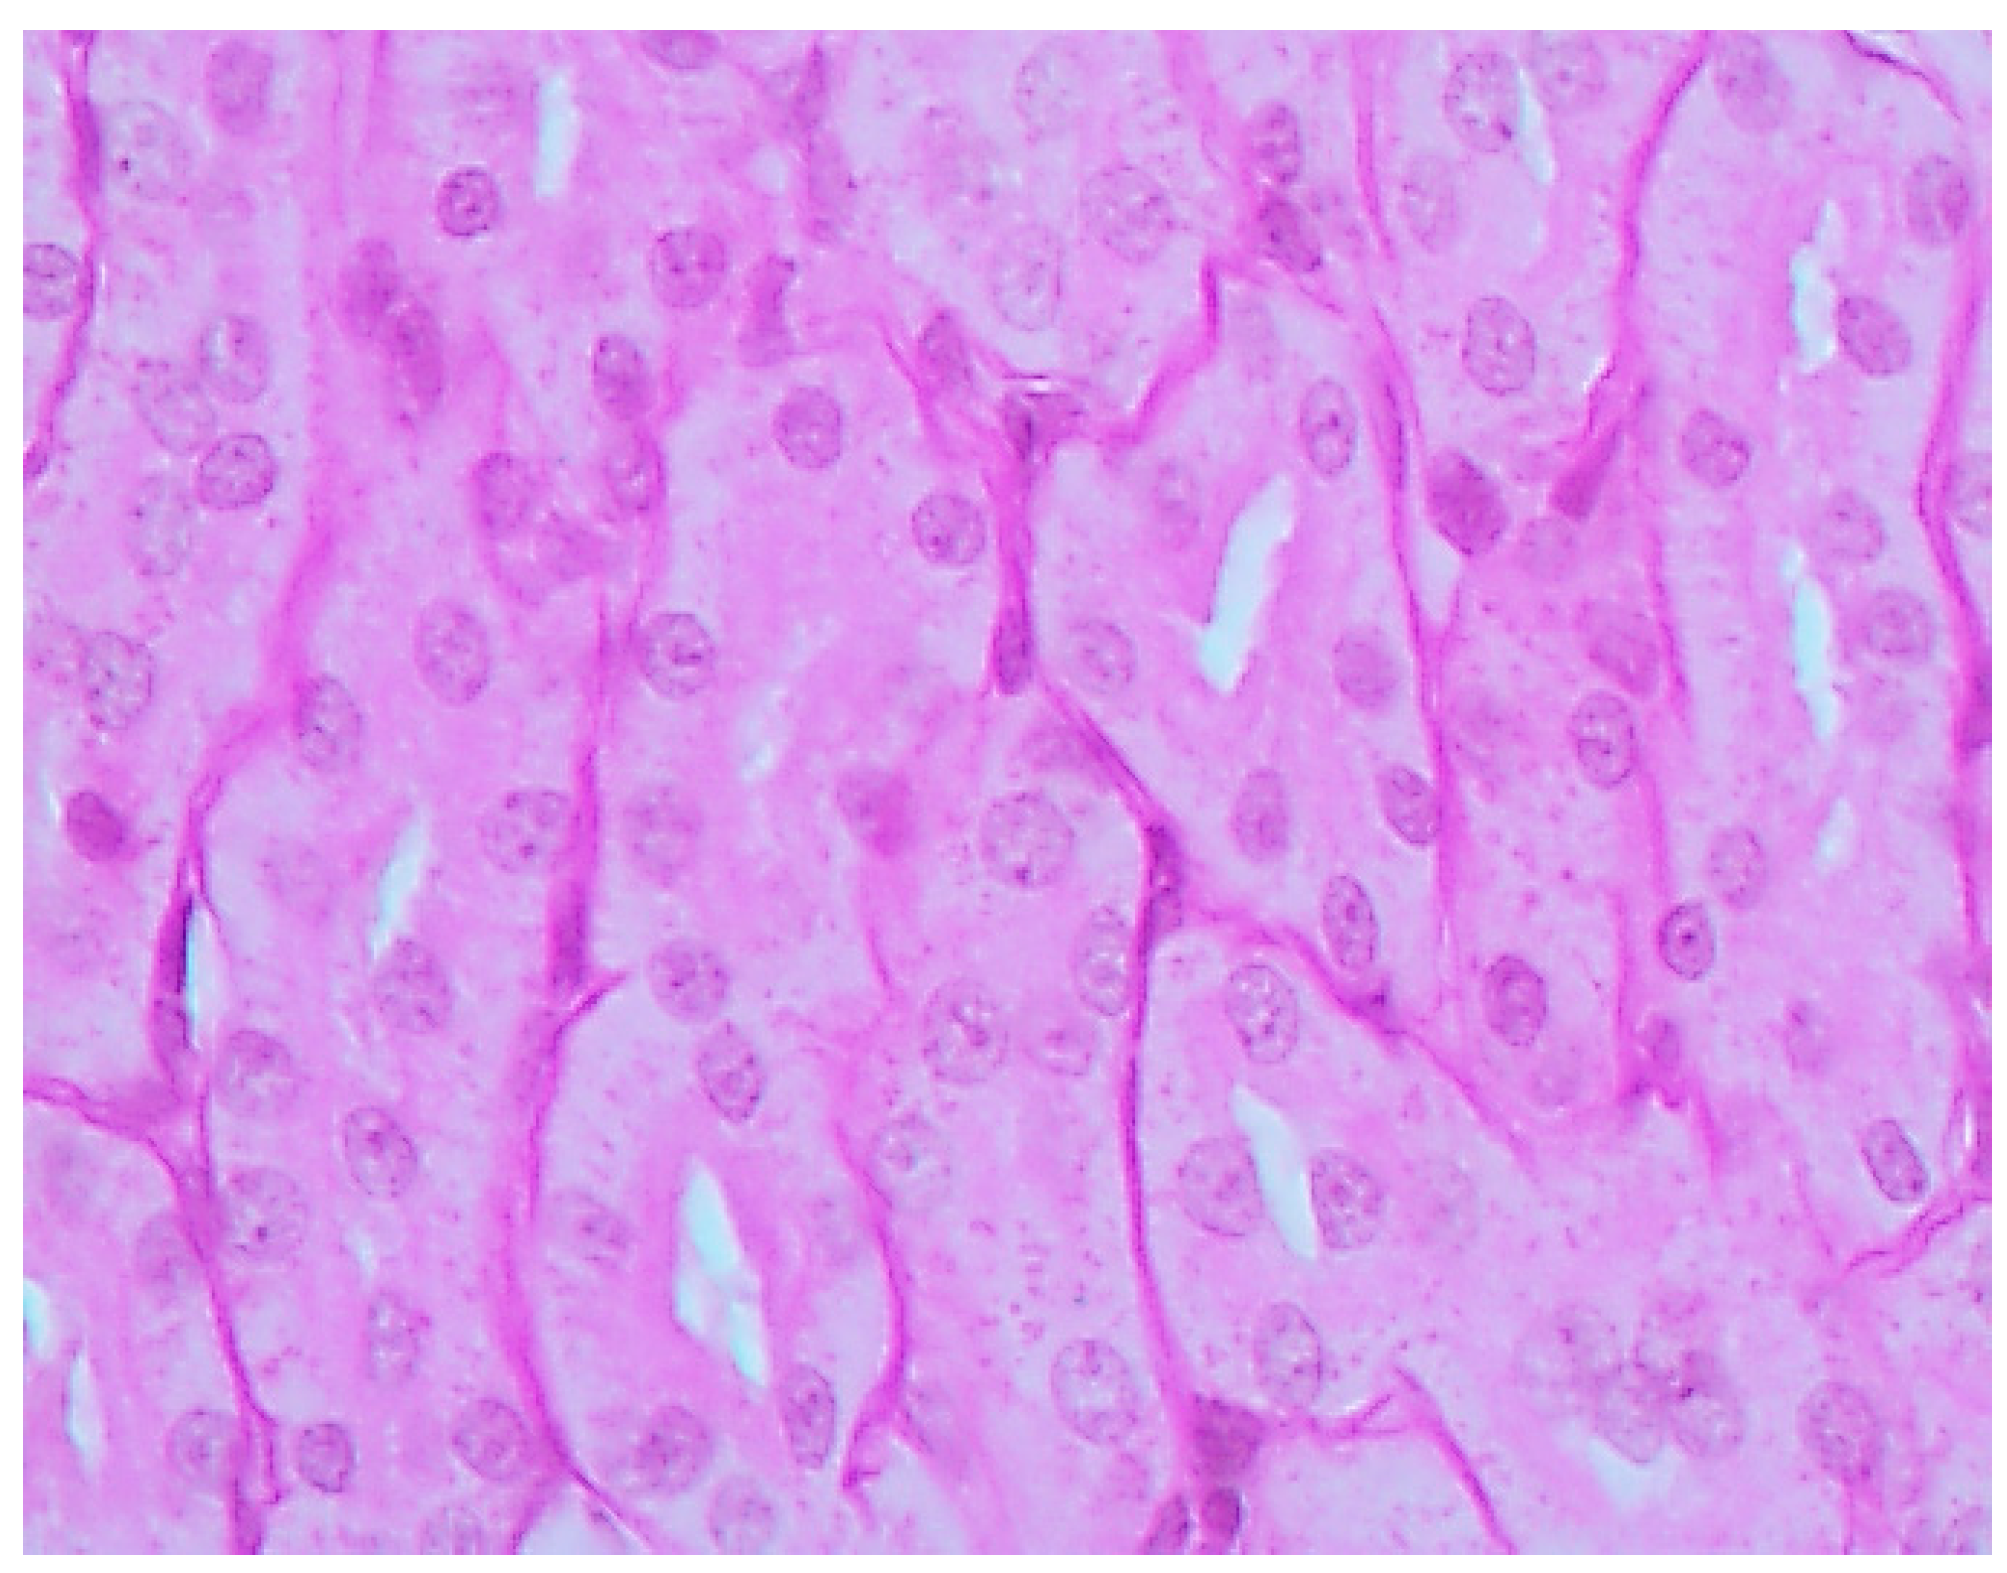

The histological picture (Figure 2, Figure 3 and Figure 4) and morphometric characteristic (Table 4) of the epithelium in the proximal convoluted tubules provide evidence of marked damage, which is a little more marked in response to NiO-NPs and, particularly, Mn3O4-NPs + NiO-NPs, than to Mn3O4-NPs alone, but is absent for the same combined intoxication with the background administration of the BPC.

Figure 4. Kidney of a rat exposed to nanoparticles of NiO and Mn3O4 together against the background BPC administration. Marked alleviation of tubular damage (compare with Figure 2 and Figure 3). PAS stain, magnification ×400.

Ijms 16 22555 g004